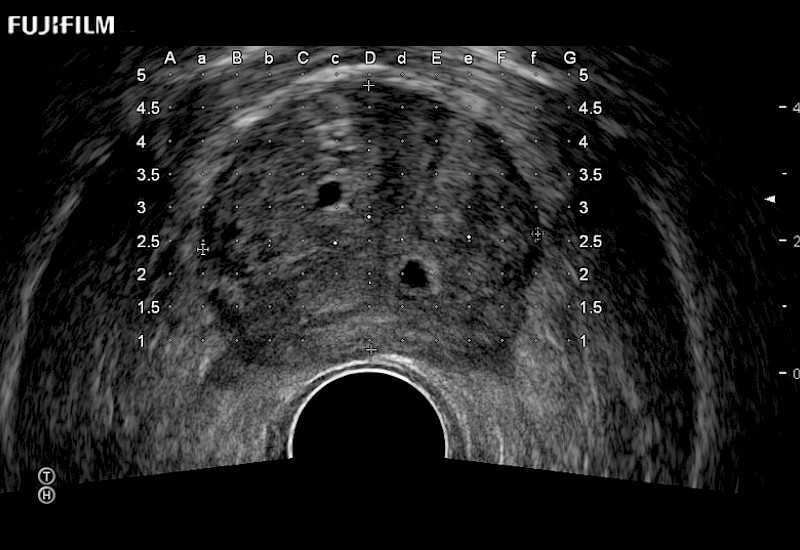

Exclusive 200° FOV end-fire prostate biopsy transducer.

Main Specifications:

Provides real-time imaging of both the sagittal and transverse planes